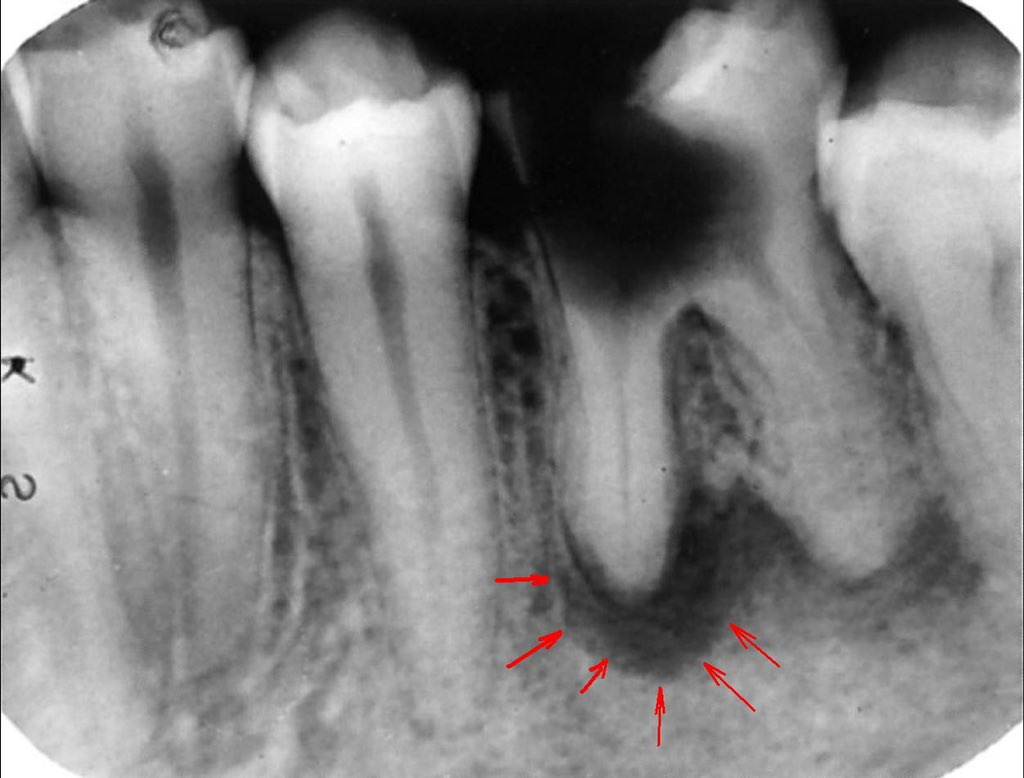

- إذا التهب العصب لفترة طويلة و ما تم علاجه يموت العصب و تبدا الالتهابات توصل لنهاية الجذور و الأنسجة الداعمة

- يبدا المريض يحس بألم وقت العض، تكون خراجات متكررة، تآكل بالأنسجة الداعمة.